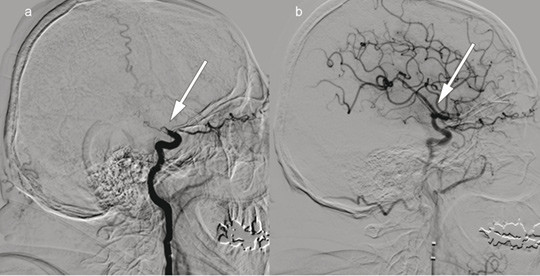

Patient 1. A man in his 70s was admitted with acute right-sided paralysis. The neurological outcome was scored on the National Institutes of Health Stroke Scale (NIHSS) to 21 points (severe cerebral infarction), and intravenous thrombolytic therapy was administered. The image to the left shows cerebral angiography with contrast injection in the left internal carotid artery, a) before and b) after embolectomy of a so-called T-occlusion (arrows) in the left carotid siphon and middle cerebral artery. The thrombus was removed and blood flow to the left hemisphere was restored 195 minutes after symptom onset. Further workup revealed atrial fibrillation and an embolic cerebral infarction in the middle cerebral artery territory. The patient received anticoagulation therapy with rivaroxaban. The NIHSS score was 0 points at follow-up three months later.